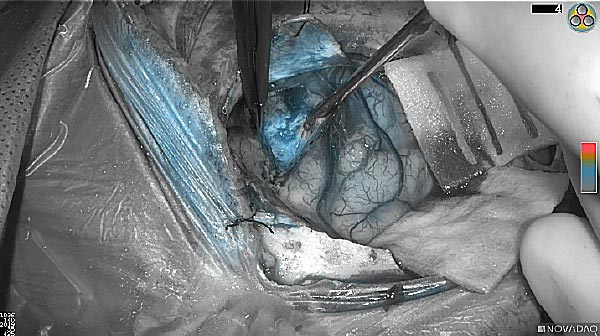

Tumor Visible

Tumor Removed

White light

Fluorescence (heat map)

Fluorescence (black and white)

As the tumor was located beneath the brain surface (as indicated in presurgical MRI), minimal fluorescence was detected through the intact dura. The tumor lied beneath the area (dashed line: expected incision path) where faint fluorescence signal showed up on the brain surface. A clear fluorescence signal was visible in the tumor when the surgeon reached the tumor (dashed circle). Very little fluorescence remained in the wound bed after surgical removal of the tumor. You may also want to read the 2019 interview with Dr. Li and Dr. Rosenthal on novel imaging technologies to identify brain cancer.